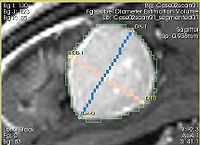

- Implementation details The module implements the following algorithm for calculating the dimensions of the label. First, the area of the label slice is computed in all the slices of the image that are passing through the label. This is done for the three orthogonal directions of the image. The largest area slice is found. The largest diameter (DA) is estimated by finding the two most distant points on the contour of the label cross-section. The second diameter (DB) is found by finding the two most distant points on the contour that lie on the line perpendicular to the first diameter. The third diameter (DC) is estimated by calculating the two points of intersection between the line perpendicular to the plane formed by DA and DBpassing through the point of their intersection, and the contour of the analyzed label.